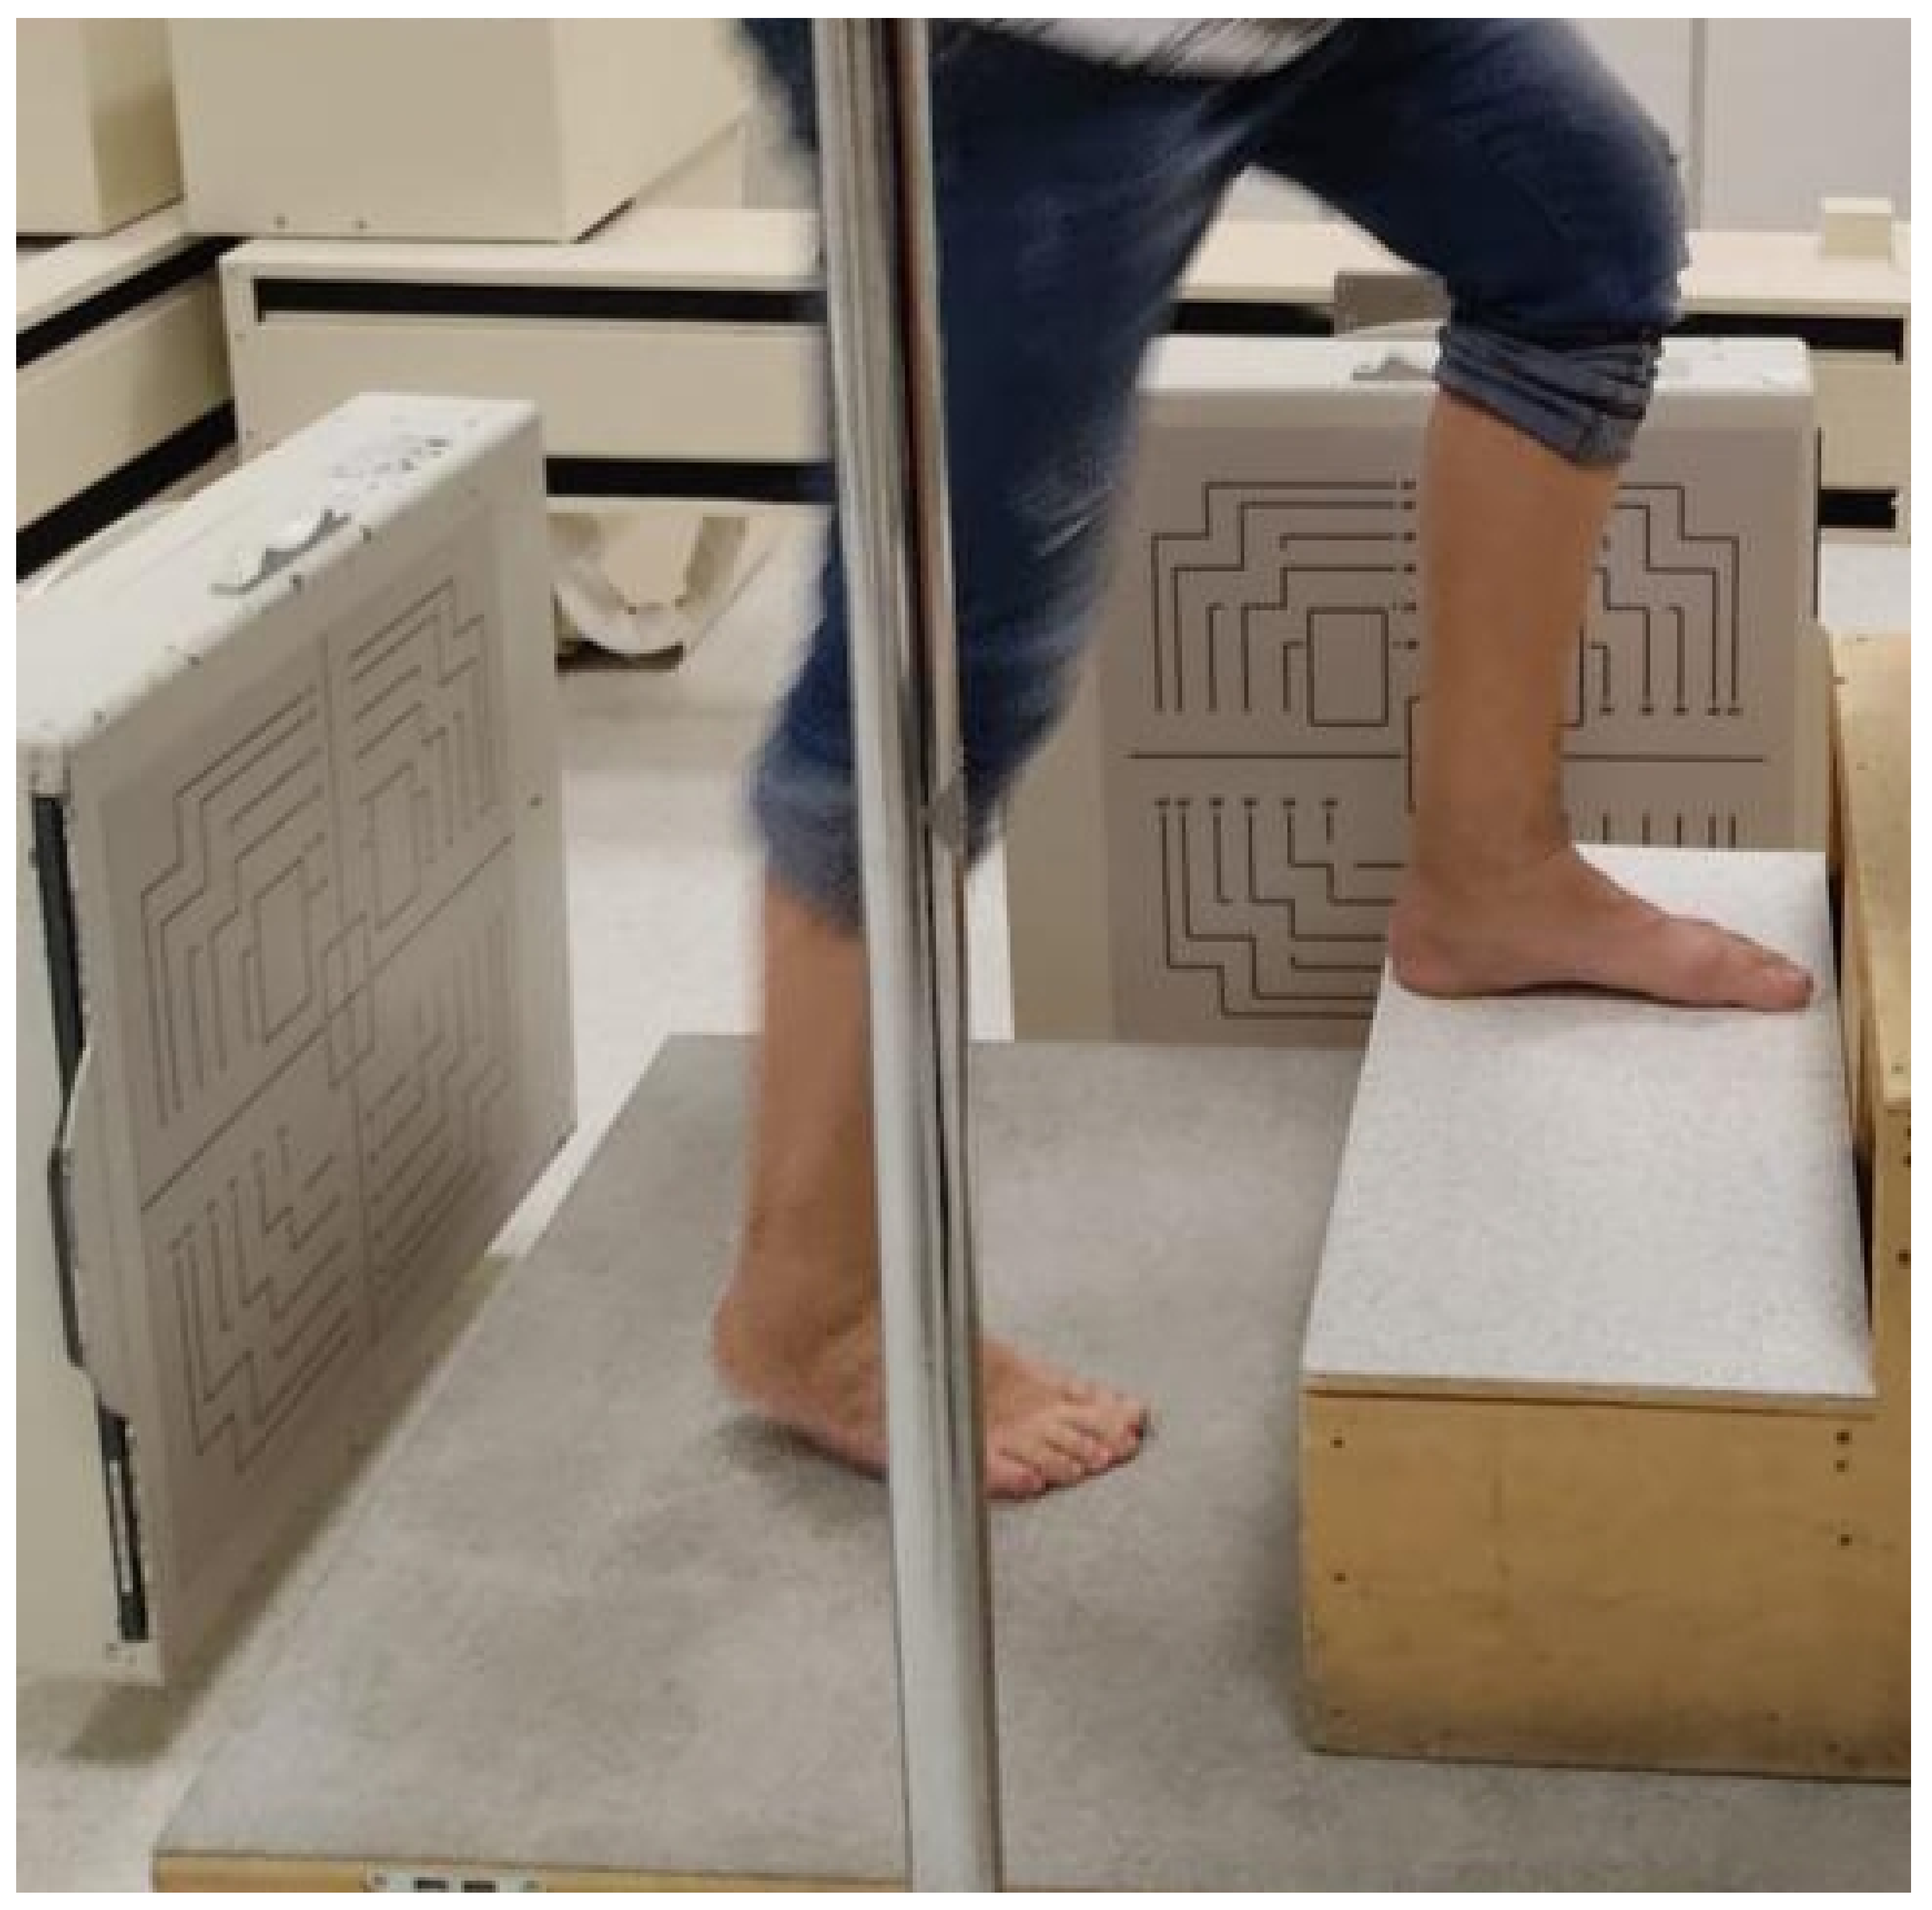

2.4. Data Collection and Measures